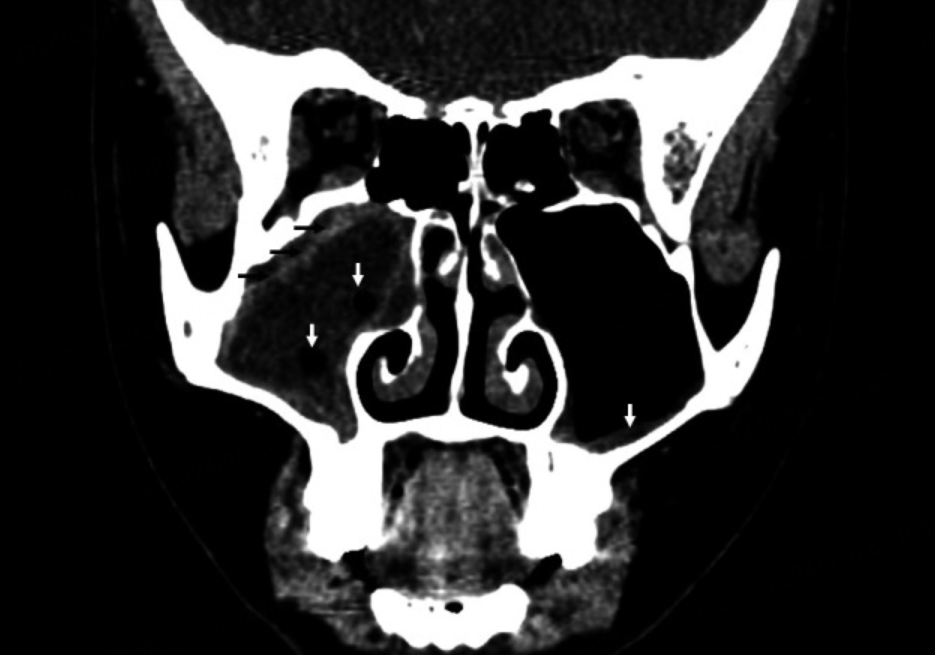

ABS中的异常X线检查结果包括鼻窦完全不透明、气液平面和受累鼻窦的黏膜增厚大于4mm(图1)[1]。需要注意的是,异常的X线检查结果无法确诊ABS,因为患有病毒性URI或其他原因引起鼻窦炎症的儿童也可能出现异常的鼻窦X线检查结果。因此,应结合临床表现来解读异常的鼻窦X线检查结果,临床医生不应凭借影像学检查来区分ABS和病毒性URI。

图1 冠状面增强CT显示右上颌窦完全不透明。注意右上颌窦积液中的黏膜增强(黑色箭头)和微小气室(白色箭头)——提示急性细菌性鼻窦炎的发现。对侧左上颌窦也有轻微的黏膜增厚(白色箭头)。

与普通X光片相比,CT扫描和MRI可以更好地显示鼻窦腔及其内容物。此外,CT扫描和MRI可以更好地评估涉及颅内空间和眼眶的并发症。美国儿科学会(AAP)和美国放射学会(ACR)建议,如怀疑有眼眶或颅内并发症,应对鼻旁窦、眼眶和大脑进行增强CT扫描和/或MRI检查。因为CT扫描无需镇静、相对方便,并且能够更好地显示鼻孔复合体和骨结构。因此,CT扫描比MRI更受青睐。